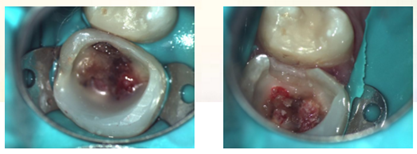

3、去净腐质后,剩余健康牙体组织位于龈下,考虑行龈壁提升,因需使用成型片,拆除橡皮障。

4、使用成型片隔离牙龈,保证边缘密合不渗漏,SDR树脂龈壁提升。

5、进行正式根管治疗前,仍需对近中邻面龋坏牙体组织进行处理。

6、上橡皮障,去除近中龋坏组织,SDR树脂制作近中邻面假壁。

7、初步恢复牙体完整性后上橡皮障,开髓,3% NaClO冲洗,揭除髓顶,修整开髓洞形,去除髓腔牙髓组织。

复诊:患者无不适,局麻下上橡皮障,去除暂封材料,结合3% NaClO冲洗,pathfile建立通路,TFA机用镍钛系统根管机械预备。根管荡洗,17%EDTA 溶液,生理盐水终末冲洗,因操作时间时间过长,氢氧化钙糊剂根管封药,玻璃离子暂封。